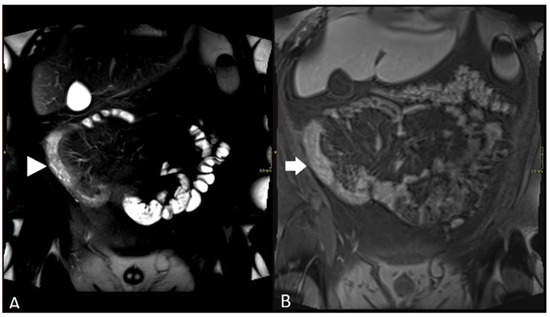

3. Motion Artifact

5. Bowel Distention